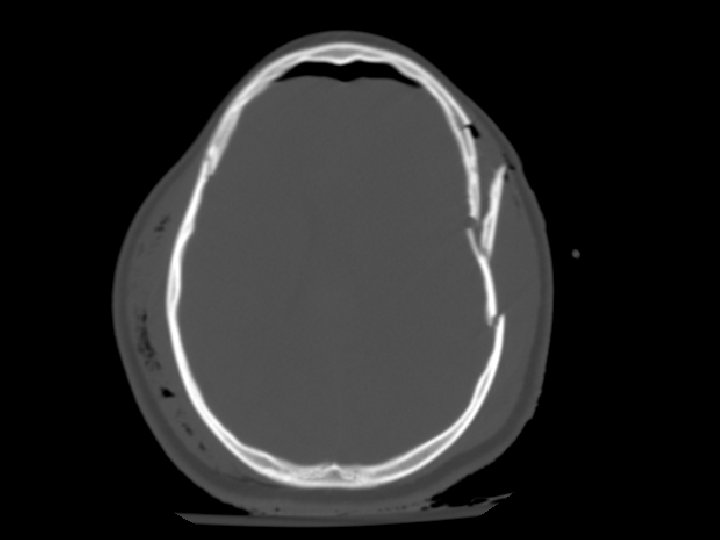

Skull Fracture • Multiple types: – Linear, depressed, and basilar • CT must be viewed on bone windows • Most important feature is injury occurring to the brain at the site of the skull fracture • Linear skull fracture: – If closed, can simply be observed

Skull Fracture • Basilar skull fracture: – Most often involving the temporal bone – Clinical diagnosis (CT often fails to show fracture) • Raccoon’s (Panda’s) eyes, hemotympanum, Battle’s sign (mastoid ecchymosis), CSF rhinorrhea • Depressed skull fracture: – Surgical elevation: • if greater than width of skull or • > 5 mm